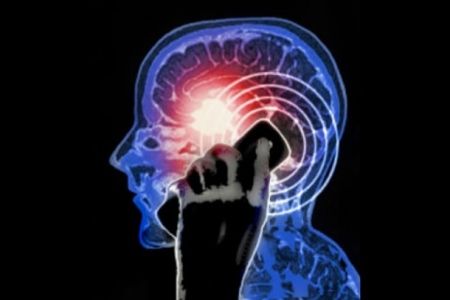

Stare parecchio tempo al cellulare fa male? Sì, fa male, potrebbe farti venire un cancro.

Beh, però guardiamo il risvolto positivo: il telefono cellulare t’arricchisce il cervello, almeno secondo quanto dicono i ricercatori dell’Istituto di Neurologia dell’Università Cattolica-Policlinico Gemelli di Roma, diretti da Paolo Maria Rossini.

Gli studiosi italiani affermano che i telefonini avrebbero la capacità di accrescere l’eccitabilità dei neuroni, soprattutto di quelli che si trovano in prossimità dell’antenna. In pratica, “elettrizzano” il cervello e modificano l’attività cognitiva, facendo in modo che alcuni processi addirittura migliorino.

Per scoprire ciò, i ricercatori hanno sottoposto alcuni soggetti a dei test cognitivi sottoponendoli nel contempo a un encefalogramma e hanno poi esposto il loro cervello alla stimolazione GSM legata ai telefoni cellulari. Secondo Rossini, l’esposizione al GSM può “in qualche maniera migliorare l’efficienza neurale“, attraverso la modulazione delle frequenze alfa del cervello, incaricate all’attenzione e alla concentrazione e influenzate in maniera positiva dalle elettromagnetiche dei cellulari.

“Quello dei cellulari potrebbe essere un effetto positivo, per esempio, in situazioni in cui l’obiettivo sia aumentare l’eccitabilità del cervello di un soggetto malato“. E si pensa ad alcune patologie cerebrali come l’Alzheimer.